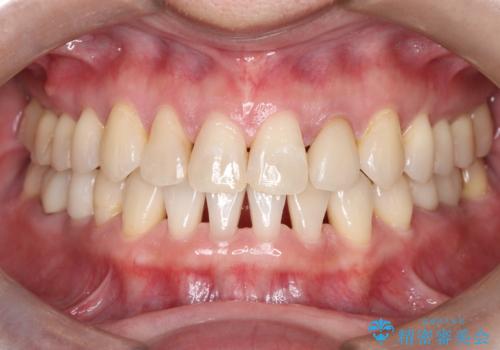

前歯の突出を防ぎながらガタつきを解消。上下左右4番抜歯による審美ワイヤー矯正

担当医 河口智英